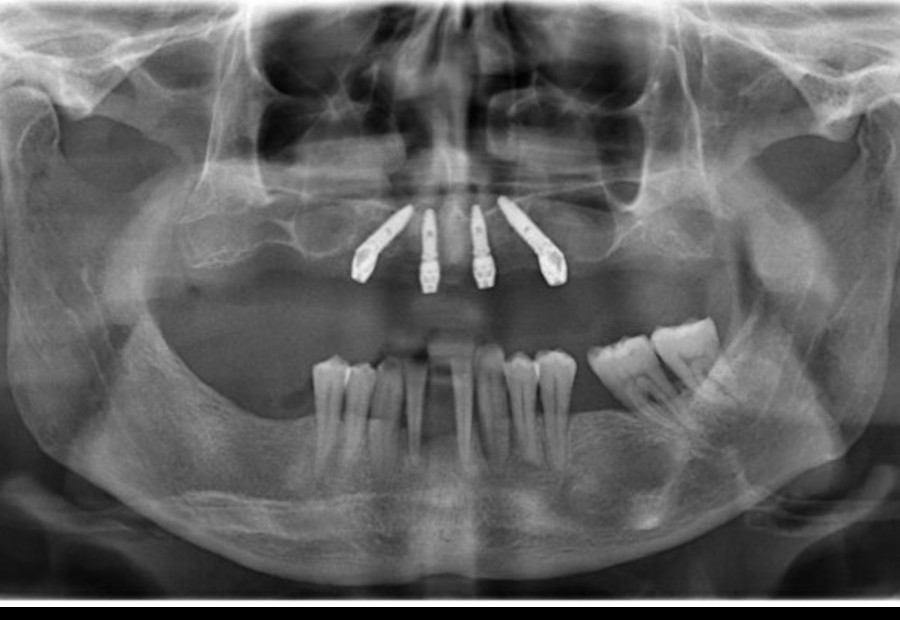

Caso 7 – Tecnica All on Four

Tecnica All on Four con carico immediato: riabilitazione totale mediante l’inserimento di 4 impianti con denti fissi avvitati. Intervento eseguito dalla nostra Dr.ssa Silvia Broglia in un’unica giornata in sedazione cosciente mediante la collaborazione di un Medico Anestesista.